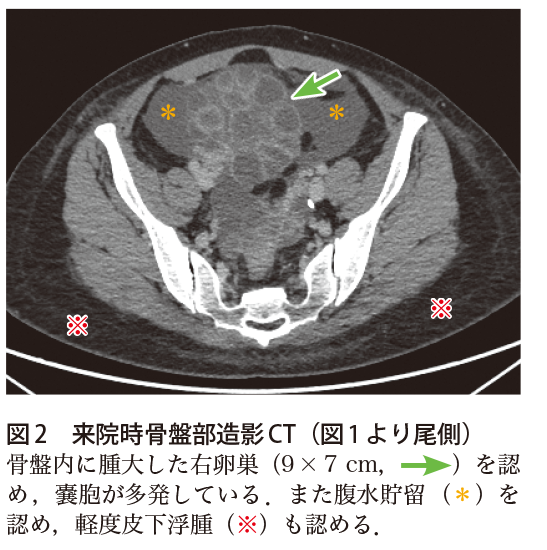

解答 解説 腹部膨満感を認める30歳代女性 実践 画像診断q A 羊土社 レジデントノート 羊土社